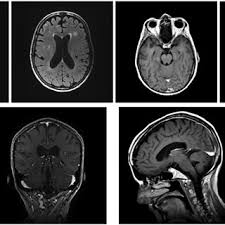

Magnetic resonance imaging MRI scan. As a result leptomeningeal disease has a poor prognosis with survival typically measured in months. Lymphomatous meningitis has a better outlook with a median survival of more than 6 months but diagnosis may be.